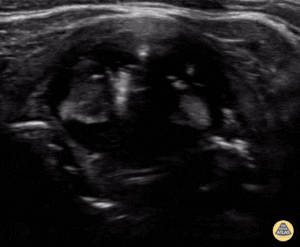

Intubation attempt into the esophagus of an 8 year old male with respiratory distress, notice the soft tissue posterior to the trachea moving with the provider attempting the pass the tube. Image contributed by: Zach Boivin, MD, @ZachBoivinMD